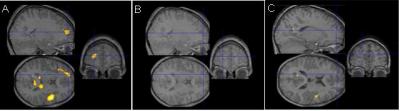

Gaab first tested how the children's brains responded to two types of sounds: fast-changing and slow-changing. These sounds were not language, but resembled vocal patterns found in speech. As Gaab watched using brain fMRI, the children listened to the sounds through headphones. The fast-changing sounds changed in pitch or other acoustic qualities quickly—over tens of milliseconds—as in normal speech. By contrast, slow-changing sounds changed over only hundreds of milliseconds.

In typical readers, 11 brain areas became more active when the children listened to fast-changing, compared to slow-changing, sounds. Gaab set this as "normal." In dyslexic children, the fast-changing sounds didn't trigger this ramped-up brain activity. Instead, dyslexic children processed the fast-changing sounds as if they were slow-changing—using the same brain areas, at the same lower intensity. "This is obviously wrong," says Gaab.

The repetitive exercises appeared to rewire the dyslexic children's brains: after eight weeks of daily sessions—about 60 hours total—their brains responded more like typical readers' when processing fast-changing sounds, and their reading improved. It's unclear, though, whether the improvement lasts beyond a few weeks, since follow-up tests were not done.